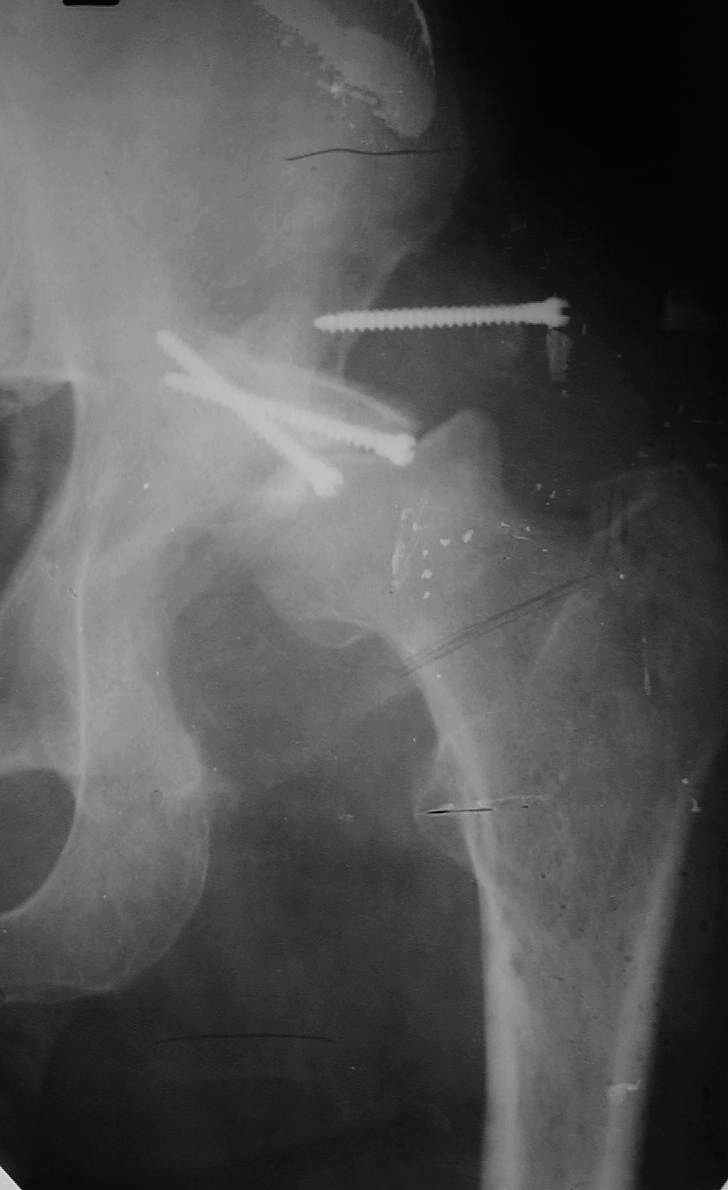

Уважаемые коллеги! На консультацию пришел молодой человек 23 лет с застарелым задним вывихомбедра. После травмы прошло 2,5 ГОДА.

Были переломы бедра и голени на этой же стороне, которые благополучно срослись после остеосинтеза. вывих бедра был пропущен. В настоящее время ходит без дополнительной опоры, есстественно, сильно хромает, выражен болевой синдром, парез седалищного нерва. Сформировался неоартроз в подвздошной области, виден неправильно сросшийся перелом задней колонны, сгибание в суставе до 80.

В институте совместно с фирмой Зиммер достаточно регулярно (практически ежемесячно) проводятся 2-х недельные циклы по различным вопросам эндопротезирования. Если есть возможность и желание, мы готовы поделиться с Вами нашим опытом, тем более есть что показать и что обсудить - в настоящее время ежедневно выполняется от 6 до 10 эндопротезирований коленного и тазобедренного сустава. В качестве примеров хочу показать 2 наблюдения, через 1 год и 5 лет после операции

1 год

5 лет